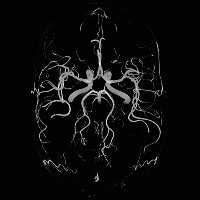

Tim technology greatly enhances cardiac examinations. The use of a 32

channel coil and new acquisition methods such as AutoViability and Cine Late

Enhancement allow for a display of the infarcted area during heart

contraction, facilitate the examination as such, and improve the diagnosis

of cardiovascular diseases with MR. Not only is it possible to obtain higher

resolution, the workflow shows considerable improvement as well: today, a

full cardiac examination of an infarcted patient can be completed within

15-30 minutes. The in the US already patented technique for precisely

displaying infarcts with Delayed Enhancement, developed together with

Raymond Kim, MD of the Cardiovascular Magnetic Resonance Center at Duke

University, Raleigh Durham, North Carolina, USA, has opened a new field of

indications, as shown by several international cooperation partners who are

now able to diagnose and differentiate various types of cardiomyopathy with

CMR. This examination helps determine the risks of an untreated patient to

die from sudden cardiac death. These statements are confirmed by the work of

Professor Dudley Pennell of the Royal Brompton Hospital in London. This

information can be an important decision-making tool for implanting a

pacemaker.